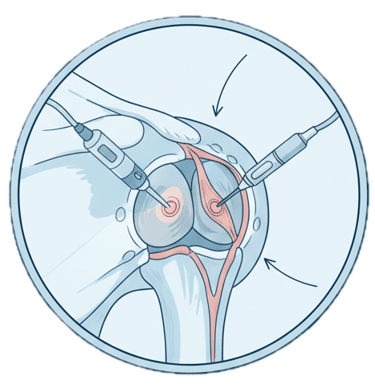

Artroscopia do Ombro

Procedimento minimamente invasivo para tratar instabilidades (luxações), lesões do labrum, síndrome do impacto e outras condições articulares.